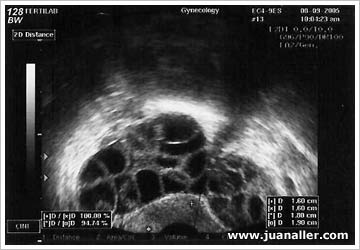

Hiperestimulación con clomifeno

Hiperstimulación con gonadotropinas